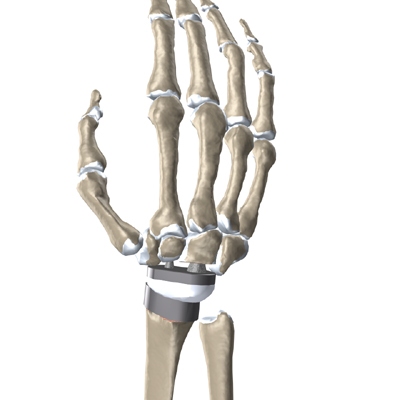

Modern artificial wrist joints are made of metal and plastic. The part that fits against the end of the radius bone of the forearm is called the radial component. It is made up of two pieces. A flat metal piece is placed on the front part of the radius. It has a stem that attaches down into the canal of the bone. A plastic cup fits onto the metal piece, forming a socket for the artificial wrist joint.

The part that replaces the small wrist bones is called the distal component. This piece is made completely of metal. It is globe shaped to fit into the plastic socket on the end of the radius. The metal distal component is attached by two metal stems that fit into the hollow bone marrow cavities of the carpal and metacarpal bones of the hand.

The plastic used in artificial joints is tough and slick. It allows the two pieces of the new joint to glide easily against each other as you move your wrist. The ball and socket allow movement of the wrist in all directions.